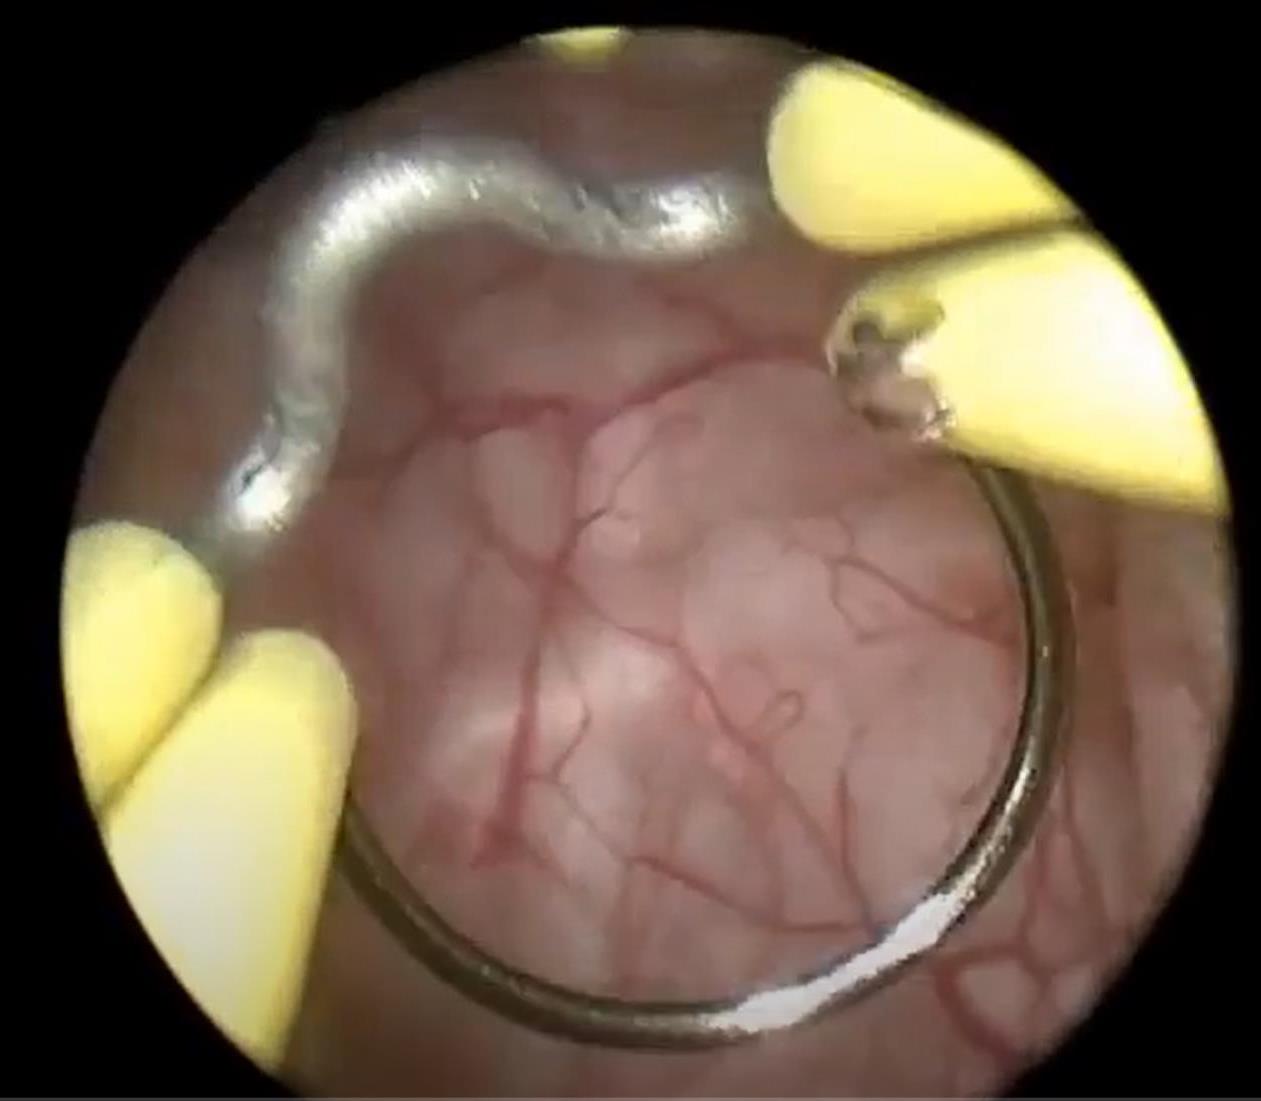

На конце резектоскопа установлена видеокамера и осветительный прибор, что позволяет отображать весь процесс на экране большого монитора.

После введения анестетика я пытался шевелить пальцами ног, чтобы понять, насколько хорошо действует анестезия. Хирург начал обрабатывать антисептиком зону операции, затем ввел смазку в мочеиспускательный канал и резектоскоп. Я ничего этого не видел, потому что между моим лицом и хирургом повесили тканевую ширму. Но я все чувствовал и пытался угадать, что именно делает хирург в данный момент. Странно, что при этом боли не было совсем.